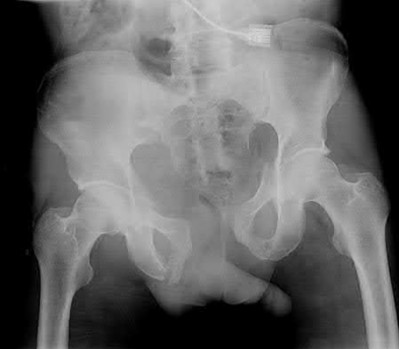

Figures and Illustrations:

Figure A is an AP pelvic radiograph demonstrating a nonunion of a femoral neck fracture after suboptimal fixation with 3 cannulated screws in a triangle configuration.

Illustration A is an AP radiograph of the left hip in this patient following conversion to THA.

Illustration B is a radiograph demonstrating a valgus osteotomy. Illustration C shows an example of a femoral neck nonunion with varus malreduction.